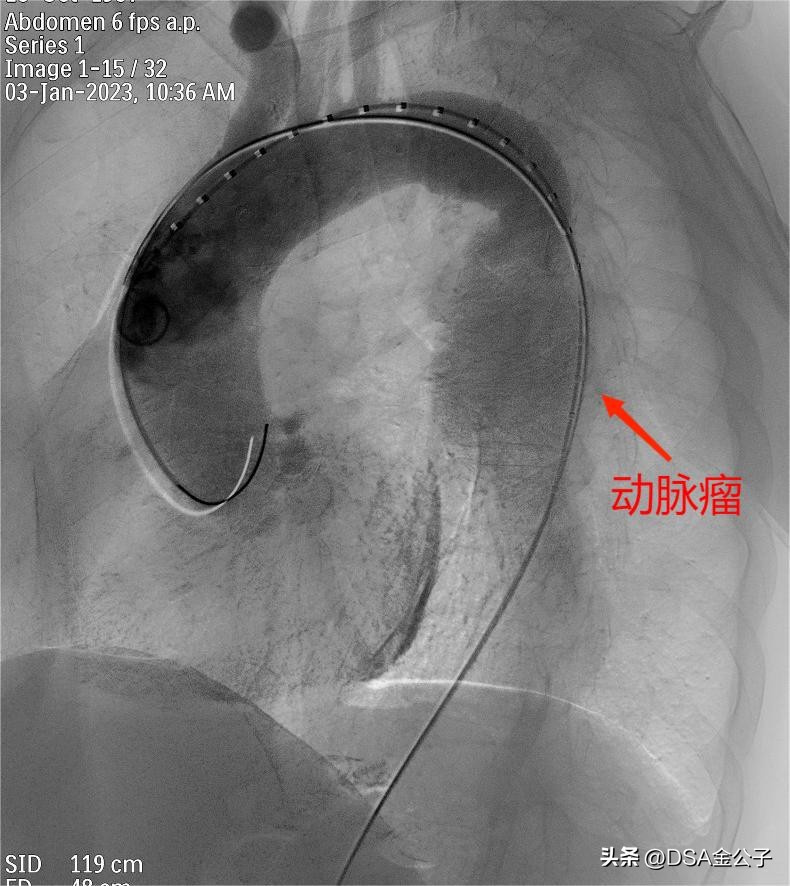

典型的降主动脉血管瘤